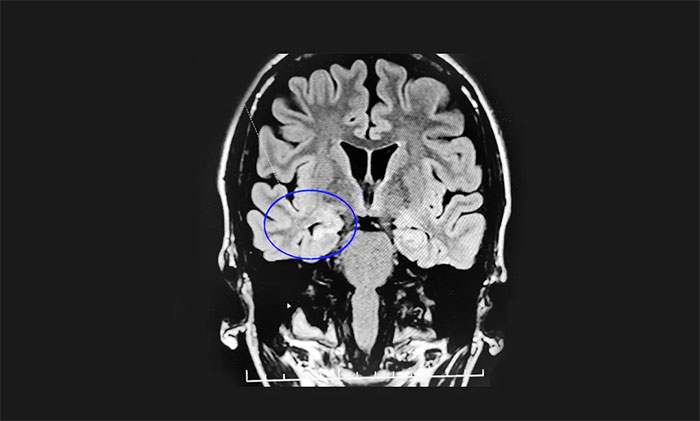

結(jié)合張女士的病史和各項(xiàng)檢查,楊忠旭教授指出,考慮張女士為腦膜炎導(dǎo)致的癲癇,并且經(jīng)系統(tǒng)內(nèi)科藥物治療不佳,確診為藥物難治性癲癇。應(yīng)用現(xiàn)代神經(jīng)影像學(xué)技術(shù)和電生理監(jiān)測技術(shù),能準(zhǔn)確定位導(dǎo)致癲癇發(fā)作的“責(zé)任病變”,手術(shù)指征明顯,未見明顯手術(shù)禁忌癥。楊教授為她制定了周全的手術(shù)方案并做好充分準(zhǔn)備。

▲ 通過系列檢查,最終明確致癲灶位

8月16日,在征得家屬同意后,楊忠旭教授在崔麗華主任腦電監(jiān)測輔助下為患者進(jìn)行了手術(shù)。切除患者張女士相關(guān)病變區(qū)域后,再次腦電監(jiān)測顯示腦區(qū)無異常放電,手術(shù)成功。目前,張女士正在康復(fù)中。